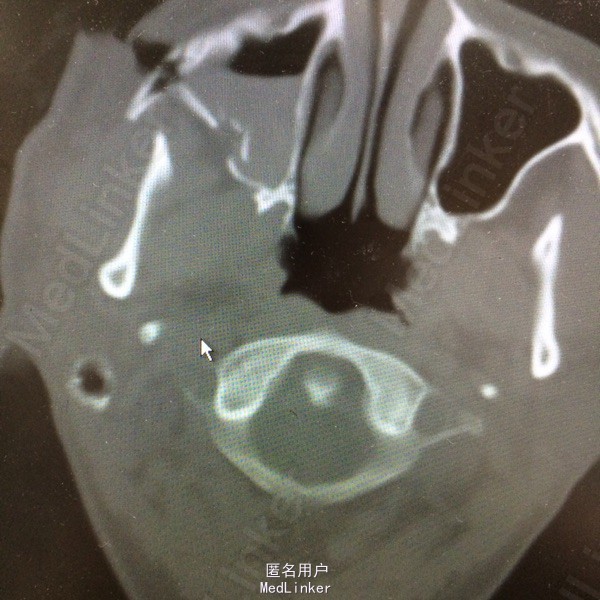

右ZMC骨折,裂伤

车祸致右面部外伤

右颧面部开放性创口,CT示右ZMC骨折。

右面部裂伤。全麻下骨折内固定,清创缝合

随访创囗愈合可,无复视与张囗受限